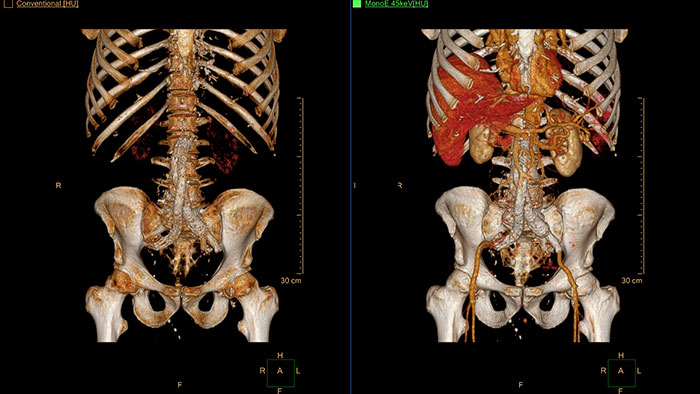

CT Spectral Light Magic Glass

Review spectral data in a range of not spectral-enhanced CT applications

Allows retrospective use of spectral data that was saved in a series of spectral base images (SBI).

The fast launch of LMG allows review and identification of the most relevant results to be launched into the application for further analysis.

- Spectral Magic Glass can be launched only for CT images or images created on the Philips IQon Spectral CT.

CT Spectral Magic Glass on PACS*

IQon Spectral CT Functionality

IQon Spectral CT is the only scanner to offer CT Spectral Light Magic Glass and CT Spectral Magic Glass on PACS, helping radiologists review and analyze multiple layers of spectral data at once, including on their PACS.

CT Spectral Viewer

IQon Spectral CT* Functionality

The spectral viewer is optimized for analysis of spectral data sets from the IQon Spectral CT Scanner. Obtain a comprehensive overview of each patient quickly and easily, quantify quickly, and assist in diagnosis. It is designed to accommodate general spectral viewing needs with additional tools to assist in CT images analysis.

- Enhances the conventional image by overlaying an iodine map.

- Visualization of virtual non-contrast images.

- Images at different energy levels (40-200 keV).